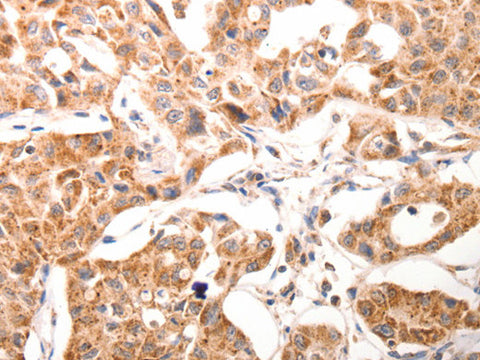

BGLAP Polyclonal Antibody Store at -20°C

Applications IHC

IHC 1:50-1:200